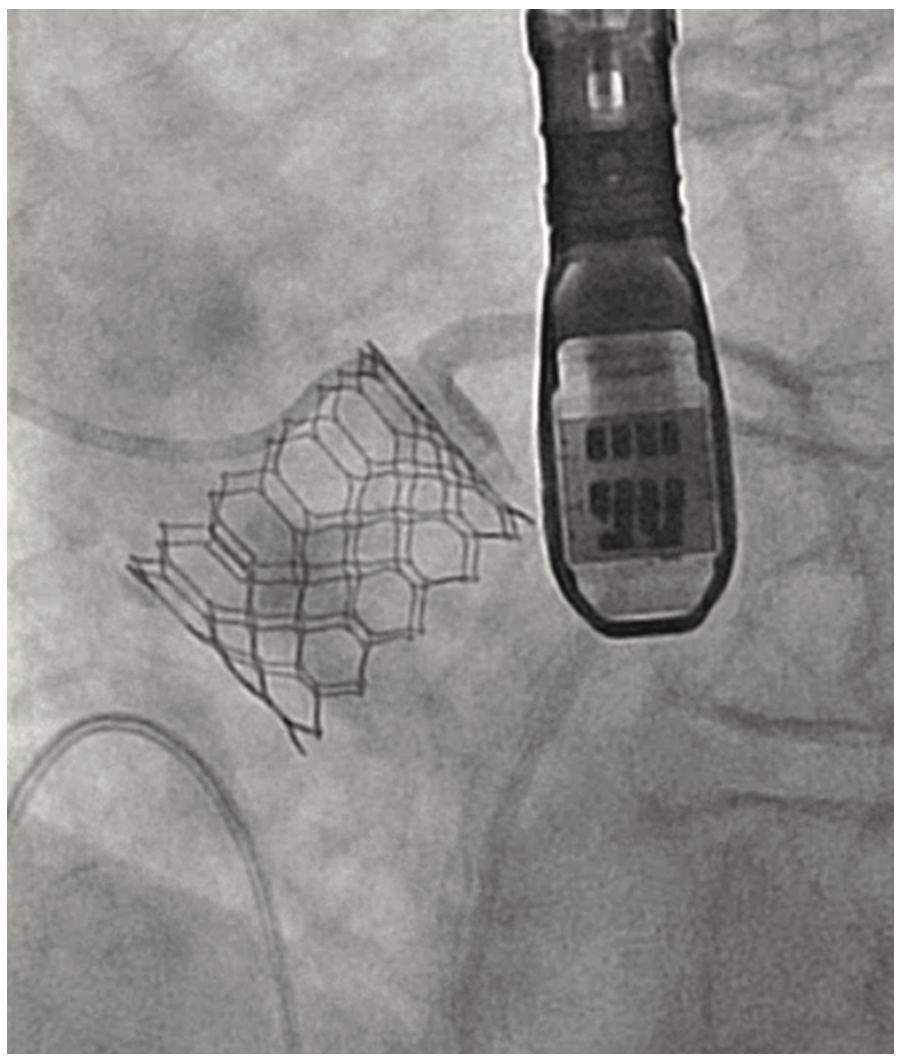

An 81-year-old female with symptomatic severe aortic stenosis, logistic EuroSCORE I (European System for Cardiac Operative Risk Evaluation) of 14.46%, EuroSCORE II of 3.44%, and Society of Thoracic Surgeons (STS) estimated surgical mortality of 3.371%, underwent TAVR. Transthoracic echocardiogram (TTE) showed a heavily calcified aortic valve with a mean gradient of 68 mmHg, aortic valve maximum velocity (Vmax) of 4.2 m/sec, calculated aortic valve area of 0.8 cm2, and normal left ventricular systolic function. Computed tomography angiography (CTA) demonstrated heavily calcified aortic root, leaflets, and annulus. Transfemoral implantation of a 23 mm Sapien 3 (Edwards Lifesciences) valve was performed (Figures 1-2). Using a 20 mm balloon for pre-dilation, the valve was implanted successfully in a 50-50 position (Figure 3). The immediate post-deployment aortogram showed leakage of dye outside the left sinus with no evidence of cardiac tamponade. Despite that fact, the patient developed immediate hemodynamic collapse. QRS widening and ST-elevation were visible on the monitor. Narrowing of the left main coronary artery (LMCA) with reduced TIMI flow (0-1) was evident in angiographic images (Figures 4-5). The patient had a cardiac arrest, cardiopulmonary resuscitation was initiated, and she went into cardiogenic shock. The patient stabilized with the placement of venoarterial extracorporeal membrane oxygenation (VA-ECMO) and the insertion of the Impella device (Abiomed) (Figure 6). An emergent percutaneous intervention was performed within minutes from collapse by the deployment of two drug-eluting stents from the LMCA into the left anterior descending (LAD) coronary artery (Figure 7) using the Culotte technique with final kissing-balloon dilatation. After the restoration of coronary flow, the patient was admitted to the cardiothoracic intensive care unit. She remained stable. The ECMO and Impella implant was removed after 7 days. Postprocedure on day 14, the patient was discharged to a rehabilitation facility. Echocardiography showed a well-functioning valve with acceptable residual gradient and mild to moderate paravalvular leak.